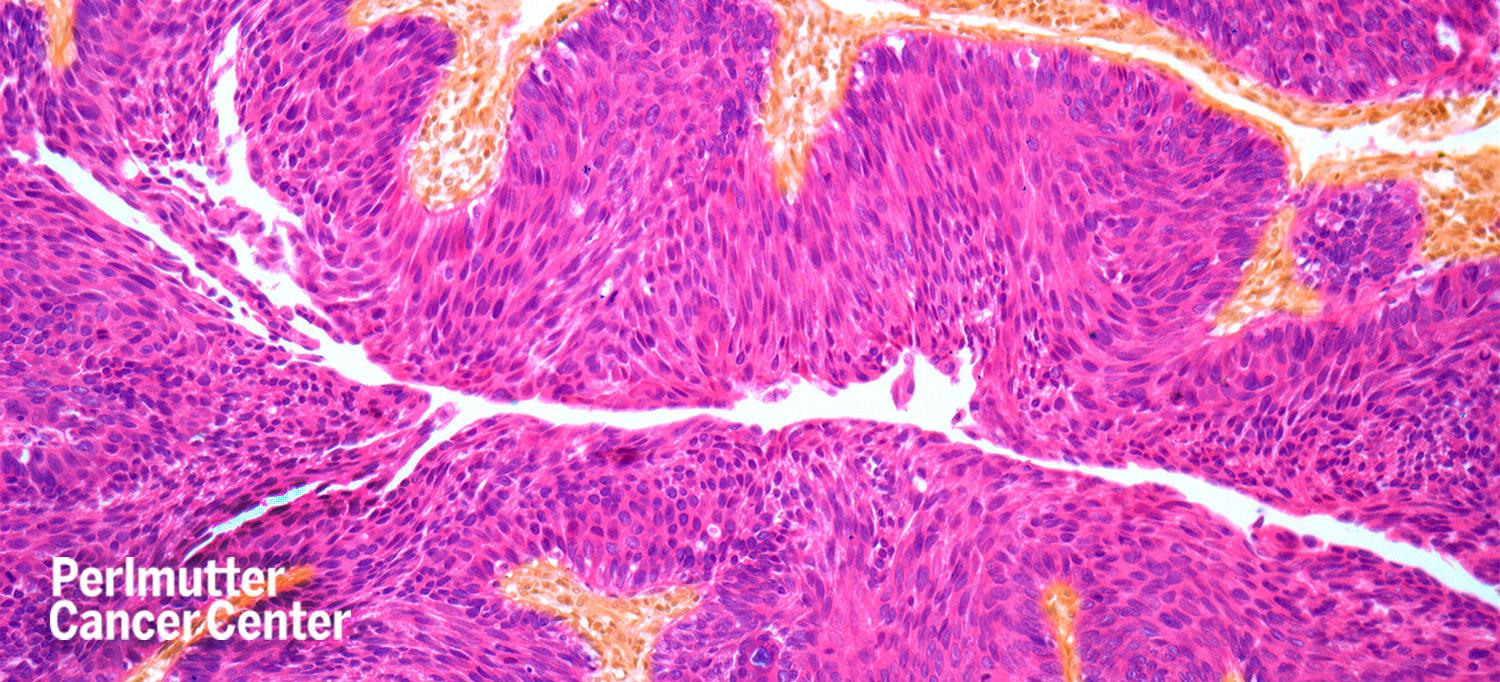

Approximately 75 percent of all patients who have bladder cancer are initially diagnosed with a form of the disease called non-muscle invasive bladder cancer, with at least half presenting with high-grade, meaning more aggressive, cancer.